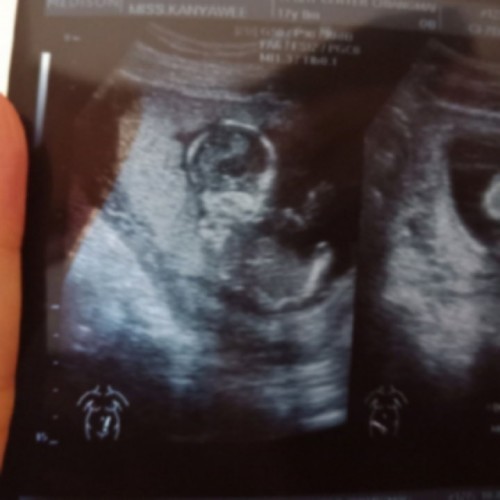

ดูไม่เป็นครับ ใครดูเป็นช่วยดูหน่อยครับ ?

ปกติเด็กในภรรค์อยู่ท่านี้ไหมครับ?

3เดือนกว่าคะ

มีหลายท่า ค่ะ

ท่าลูกผมเห็นแล้วปวดคอเลยครับ5555

ปกติค่ะ